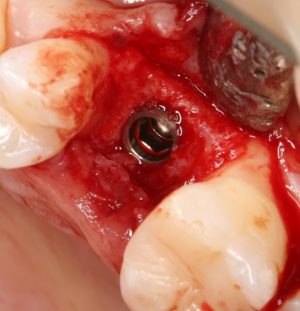

Рекомендации по установке имплантов. Для всех. Часть III